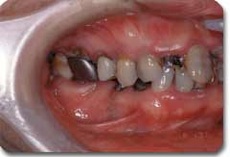

かみ合わせ治療前の状態です